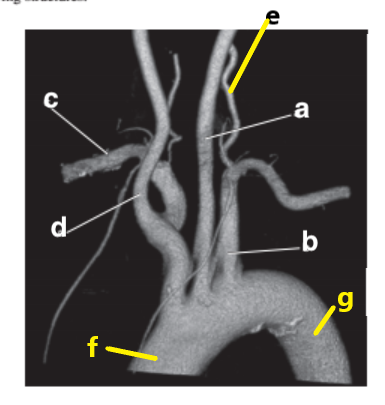

Which letter is the Descending aorta ?

f

Which letter is the Right vertebral artery ?

Which letter is the Left common carotid ?

b

Left vertebral artery

Which letter is the left subclavian artery ?

Which letter is the Right common carotid artery ?

d

Brachiocephalic trunk

c

Which letter is the right subclavian artery ?

g

a

Which letter is the brachiocephalic trunk ?